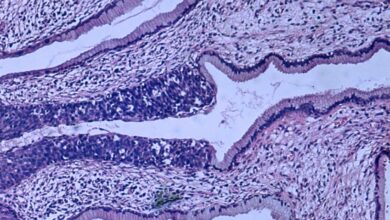

Risco de câncer cervical é duas vezes maior em mulheres com doença mental

Displasia de alto grau (carcinoma in situ) no colo do útero. O epitélio anormal está se estendendo para uma glândula…